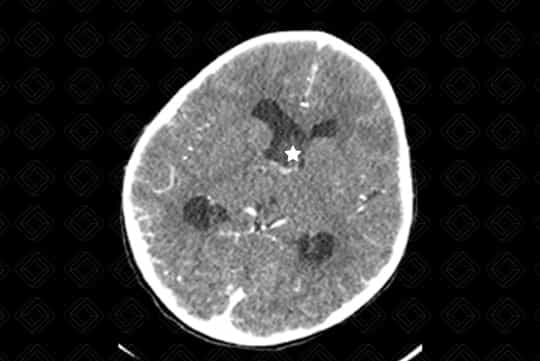

Texto alternativo para a imagem Figura 1. Créditos: Dra. Elazir Mota - Rio de Janeiro/RJ

Descrição das figuras 1, 2, 3, 4 e 5: Tomografia computadorizada do crânio após administração do contraste venoso nas reformatações axial e coronal. Paciente de 4 anos com lesão discretamente captante de contraste (asterisco - figura 2) no corno anterior do ventrículo lateral direito, causando obstrução do forame de Monro e hidrocefalia secundária, de etiologia obstrutiva. [cms-watermark]